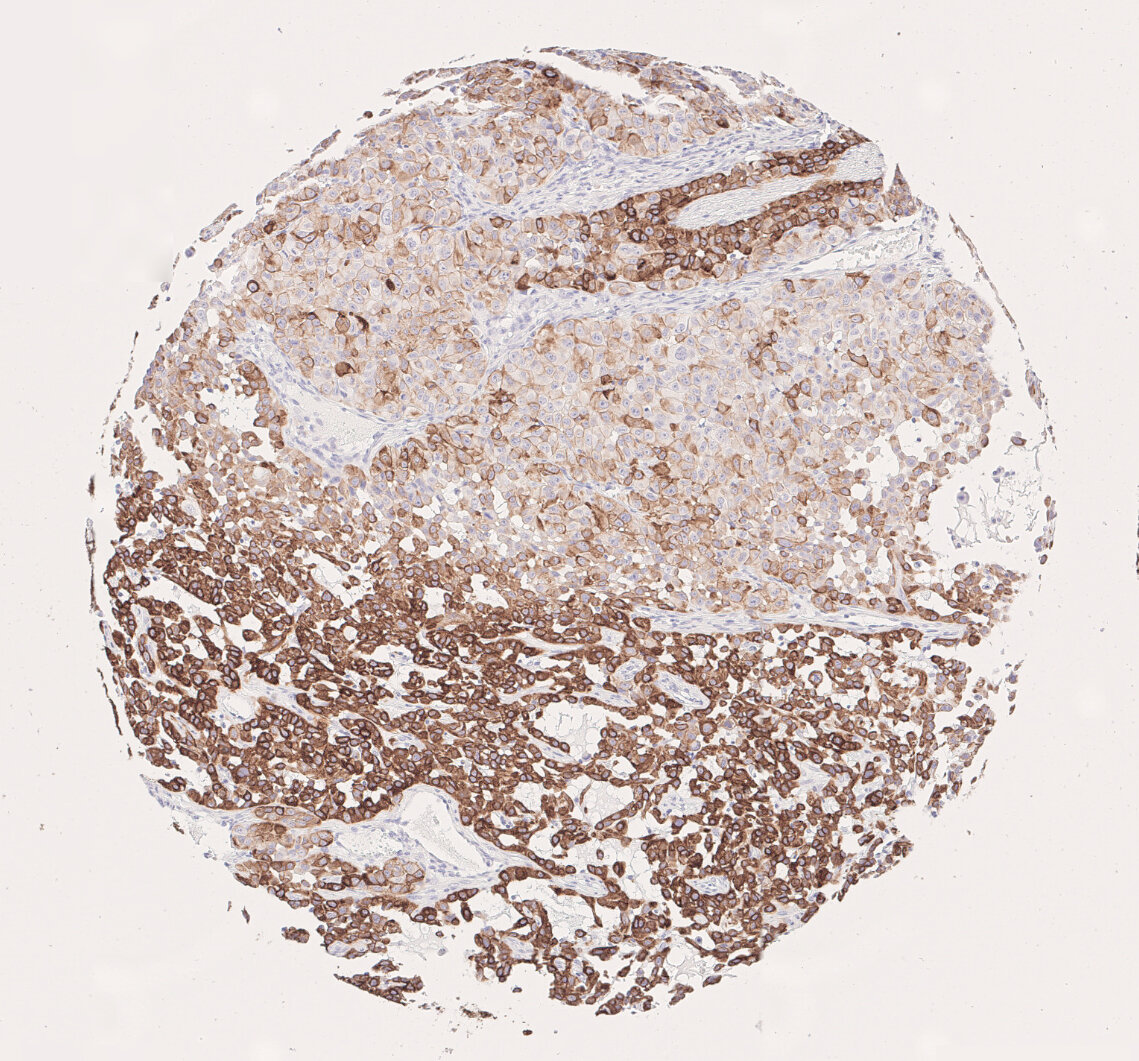

CK7 immunohistochemistry visualizes tumor heterogeneity in NSCLC adenocarcinoma subtype in a brownish color

Figure 6: CK7 immunohistochemistry visualizes tumor heterogeneity in NSCLC adenocarcinoma subtype.

In summary, RNAseq scores and CK7 staining stores yielded comparable results in the present study. High RNAseq scores correlated with medium to high CK7 expression scores in IHC-P. In addition, CK7 expression analysis using immunohistochemistry visualizes tumor heterogeneity. This spatial information is lost in RNAseq. (Figure 6).